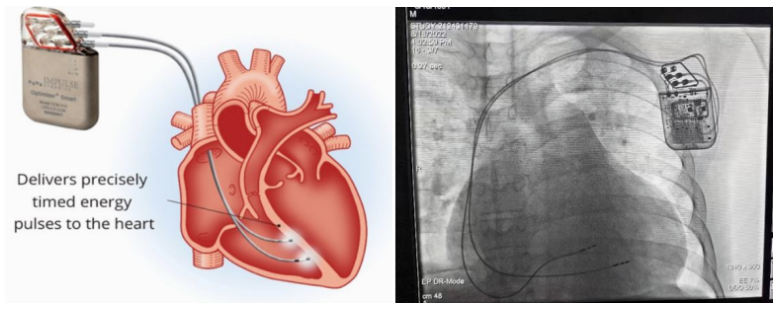

①植入式心臟復(fù)律除顫器

Implantable Cardioverter Defibrillator,ICD

植入式心臟復(fù)律除顫器是一種具有除顫功能的高級(jí)起搏器,是一種體積小、能植入患者胸部皮下組織的醫(yī)療設(shè)備。慢性心衰患者易發(fā)生室性心動(dòng)過(guò)速或心室顫動(dòng),導(dǎo)致心源性猝死(SCD)。ICD 則能在幾秒內(nèi)自動(dòng)識(shí)別并治療快速室性心律失常,通過(guò)低能量心臟轉(zhuǎn)復(fù)和高能量除顫等功能,顯著降低惡性室性心律失常引起的猝死風(fēng)險(xiǎn)??杉皶r(shí)自動(dòng)為患者轉(zhuǎn)復(fù)心律,通俗地說(shuō)就是裝在體內(nèi)的自動(dòng)除顫儀。

心臟再同步化治療,指雙心室起搏器,是通過(guò)雙心室同步起搏的方式,幫助心衰患者實(shí)現(xiàn)正常起搏的裝置。CRT包括一個(gè)口袋大小的脈沖發(fā)生器和三根電極導(dǎo)線,可被植入人體。通過(guò)監(jiān)測(cè)心律,在發(fā)現(xiàn)異常后,信號(hào)發(fā)生器發(fā)送電流脈沖,刺激心室重新同步,從而改善癥狀,提高患者的心臟泵血效率。目前有兩種類型的CRT裝置:植入式心臟再同步治療起搏器(CRT-P)和植入式心臟再同步治療除顫器(CRT-D)。主要區(qū)別在于后者除了改善心臟收縮同步性外,還具備除顫功能,能及時(shí)處理危及生命的室性心律失常,避免猝死。